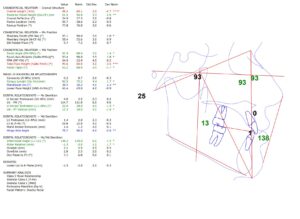

En nuestro Centro radiológico dental, contamos con equipamiento de vanguardia para ofrecerte los mejores resultados en radiografías dentales, radiografías panorámicas dentales, tomografía dental 3D y muchas más. Nuestro equipo de odontólogos está capacitado para brindarte la mejor atención para que tu dentista pueda tomar decisiones informadas sobre tu tratamiento. Además, nuestra radiología digital dental garantiza imágenes de alta calidad y reducción de daños por radiación. Si necesitas una radiografía panorámica dental, no dudes en visitarnos. Contáctanos para conocer nuestros precios y horarios de atención.